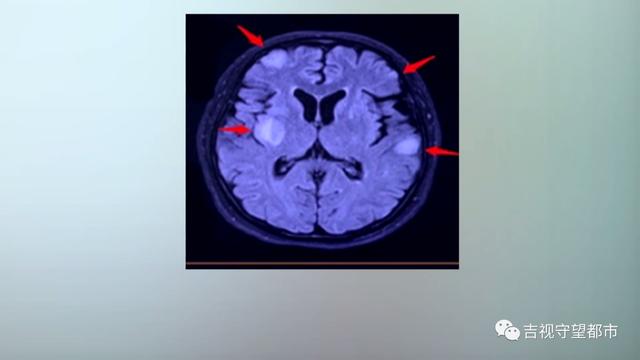

根据医生介绍 , 该名患者核磁共振结果发现 , 颅内散在类圆形病灶30余处 , 其中有4处病灶靠近皮层 。

简单的说 , 像馒头长毛一样 , 分布在整个颅内 。